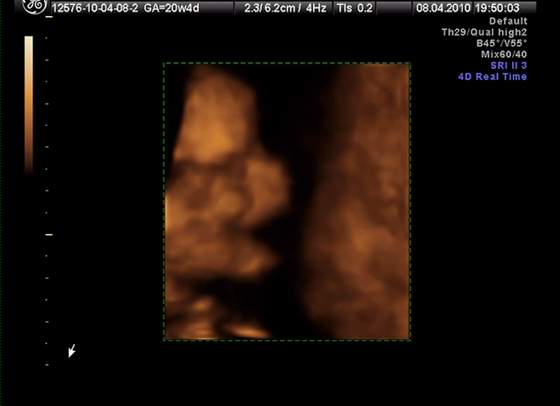

śliczna panienka rośnie :-)Przyszła kolej na moją śliczną córunię - mam nadzieję, że już jej nic nie wyrośnie, bo się przyzwyczaiłam... :-)

kolejno: uśmiech, pipulka, twarzyczka i krągła dupcia